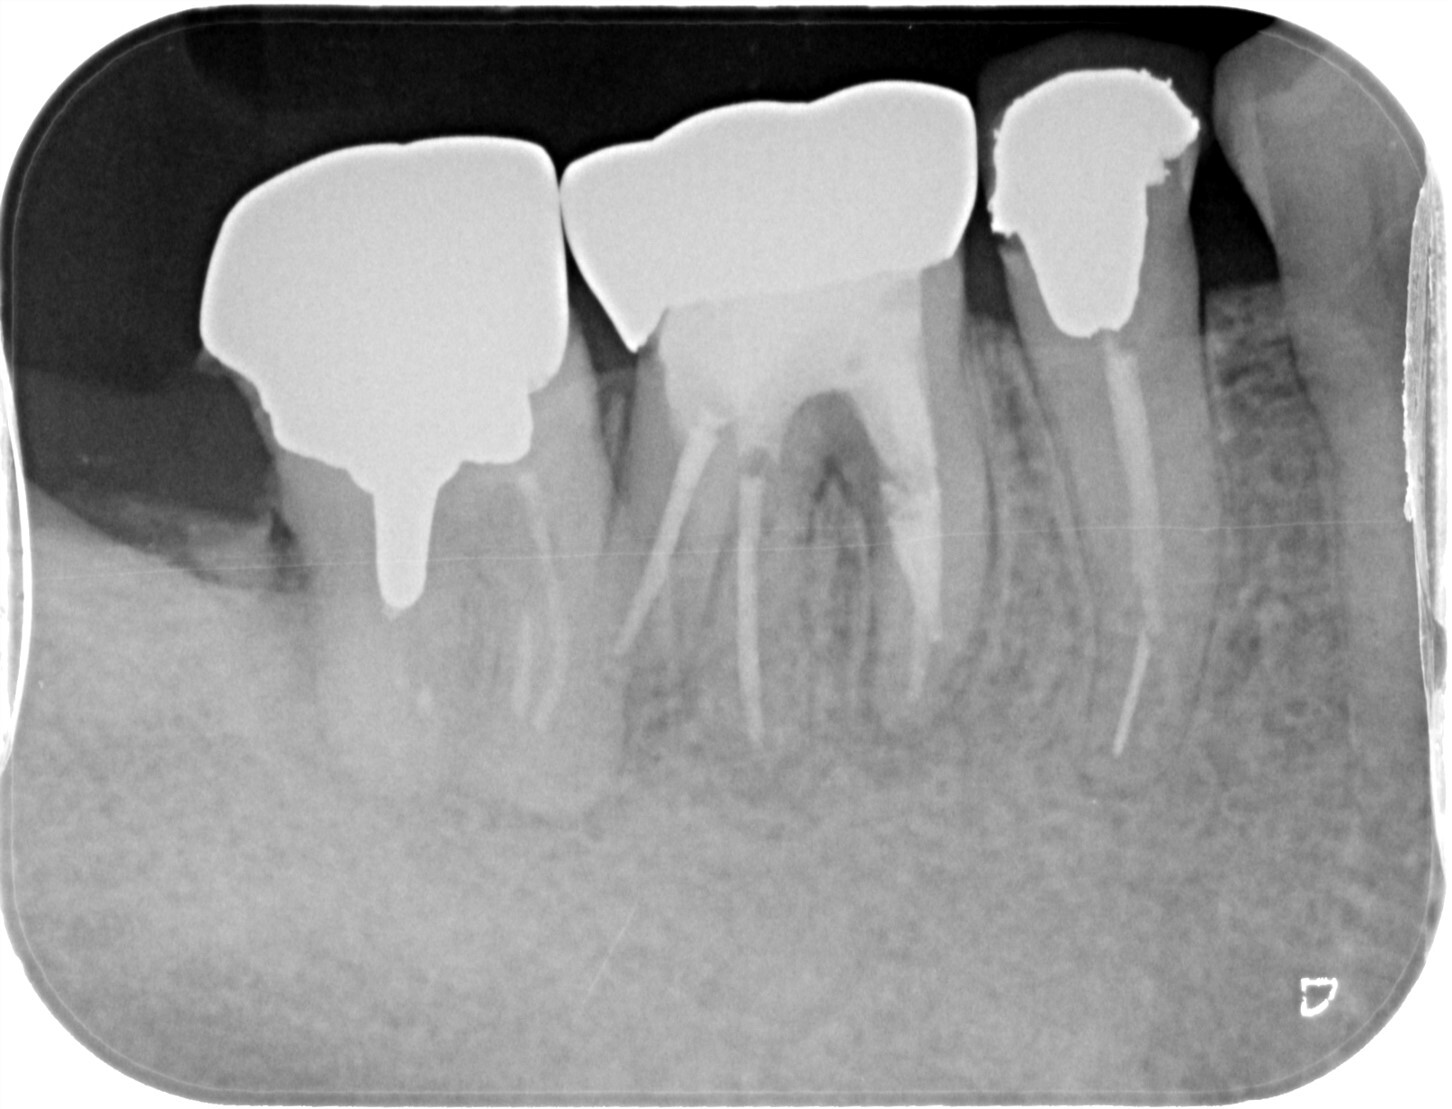

| 主訴 | 過去の治療にて根管充填後、噛むと違和感・痛みが出てきた。一度詰めた薬を撤去してもらったが症状が変わらなかったため来院。 |

| 治療内容 | ラバーダム防湿を行い、マイクロスコープにて根尖部の溢出ガッタパーチャの除去を行いました。 |

| 想定されたリスク | ガッタパーチャが取り切れない可能性がある。除去したとしても違和感・痛みが続くこともある。 ガッタパーチャを取ることにより根尖が過拡大されてしまい、根管充填時に更なる溢出を起こす可能性がある。 MTAセメント根充や外科的な処置が必要となる可能性がある。 |

CT撮影により根尖部にガッタパーチャの溢出を確認。

拡大視野下にて残存ガッタパーチャを確認しながら過拡大に注意しながら除去。

その後根管充填を行った症例です。ガッタパーチャ除去したことで症状が改善されました。